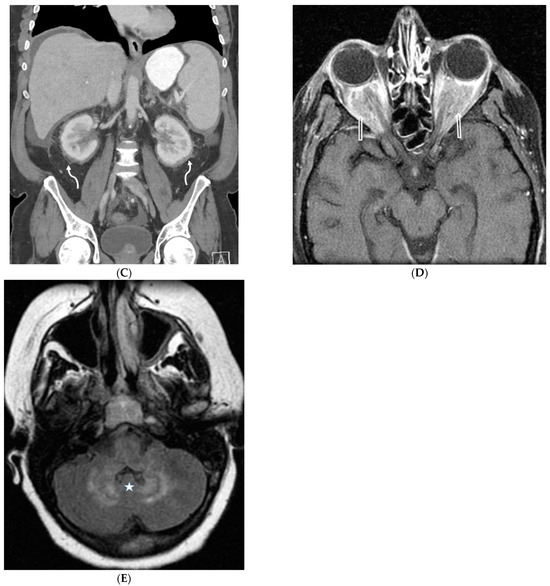

8.4. Erdheim Chester Disease (ECD)

8.5. Niemann–Pick Disease (NPD)

- Wittenberg, K.H.; Swensen, S.J.; Myers, J.L. Pulmonary involvement with erdheim-chester disease: Radiographic and CT findings. Am. J. Roentgenol. 2000, 174, 1327–1331. [Google Scholar] [CrossRef]

- Resnick, D.O.; Greenway, G.U.; Genant, H.A.; Brower, A.N.; Haghighi, P.A.; Emmett, M.I. Erdheim Chester disease. Radiology 1982, 142, 289–295. [Google Scholar] [CrossRef]

| Erdheim Chester disease (ECD) | smooth, diffuse, sometimes nodular | + | + | + | − | + | − | − | − | + |